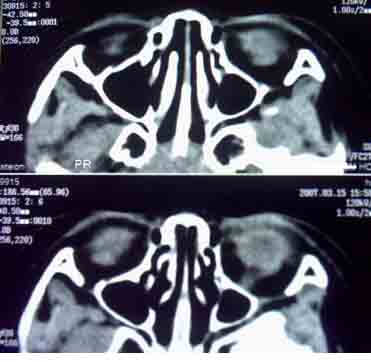

患者,偶然发现左眼无光感,平时,无明显不适,眼外观无明显异常。

ct检查:(1)眼内高密度肿块:(2)肿块内钙化斑,30~90%病例有此发现可作为诊断根据;(3)视神经增粗,视神经孔扩大,说明肿瘤向颅内蔓延。

1.ct表现:眼球内均匀高密度肿块,有增强,并多有点状或团块状钙化,在3岁以下的儿童有极大的诊断价值。可见相关视网膜下积液。

鉴别诊断 :需与渗出性视网膜病鉴别。